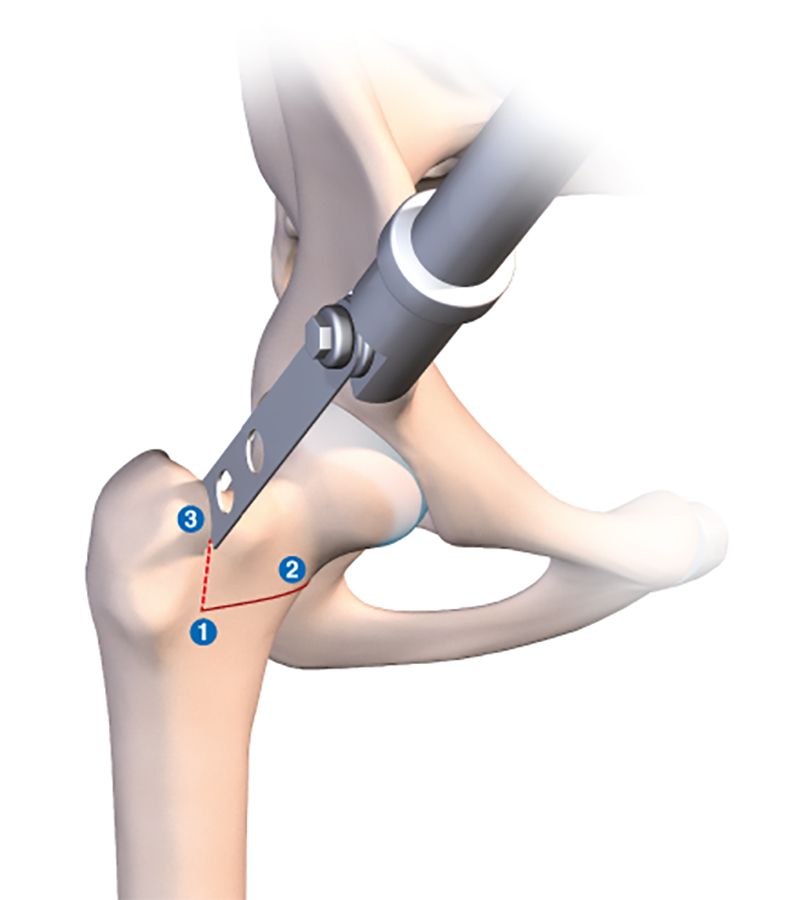

This technique is also very useful for version correction osteotomies at the base of the neck to treat excessive anteversion of the femoral neck. The problem can be corrected at the point of the problem instead of at the femoral diaphysis as when using an intramedullary nail. The need for rotation requires complete mobilisation of the neck, involving a double osteotomy line in order to avoid mobilising the greater trochanter. The first horizontal line terminates at the lower insertion of the greater trochanter on the trochanteric tubercle (Figs 4b and c), with the second line running perpendicular and vertically terminating in the greater trochanter (Fig. 4d) just behind the origin of the femoral neck, leaving the periosteum intact. The line is usually incomplete.

In order to guarantee avoiding the blood vessels when creating this second vertical line, I recommend resection of the anterior cortex only. This will leave a posterior bony hinge to protect the median circumflex vessels.

The foot is placed in sharp medial rotation, then an osteotome is inserted into the vertical line. The foot and knee are then returned to neutral rotation (Fig. 4e). The osteotome holds the neck in medial rotation by opening the derotation osteotomy. The posterior cortex will break naturally and automatically create a posterior hinge.

No tool or instrument should bypass this potentially dangerous region. If the vertical line is sufficiently posterior, there is no great risk since the vessels run in close contact to the femoral neck (Fig 4a). It reaches the neck after passing between the medial and lateral obturator muscles.

Before making the two osteotomy lines, the whole procedure can be made easier by drilling a 3.5mm hole in the anterior cortex anterior to where the two perpendicular lines will join, then using an image intensifier to ensure the optimal positioning of the two osteotomy lines (Fig 4b).

With derotation osteotomies, we always fill open lines using a small allograft fragment (Figs 4f and g).